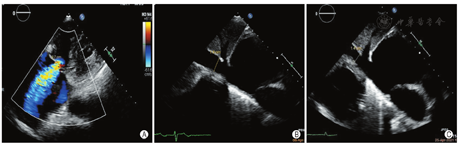

手术过程:患者于复合手术室取平卧位,常规消毒铺巾,静脉复合麻醉后。①穿刺左侧桡动脉监测血压,穿刺右侧股动脉/股静脉分别置入6F/6F鞘管,右冠状动脉造影正常,然后于右冠状动脉内放置冠状动脉导丝(ASAHI SION PTCA Guide wire,0.014″×180 cm)以标记右冠状动脉与三尖瓣后瓣环的空间位置关系。②穿刺右侧颈内静脉,预置1把ProGlide后,穿刺置入9F鞘管,然后进入Amplatz Superstiff (Amplatz Superstiff J Tip Guider wir,0.035′×260 cm)导丝,并在二维(2D)TEE食管中段上下腔切面监测下将导丝置入下腔静脉入口处(图3),退出9F鞘管,将18F K-clip可调弯鞘(下称大鞘)在2DTEE和(或)三维(3D)TEE食管中段上下腔切面监测下缓慢推进至右房中下部(图4),并固定于无菌床头固定器上。③沿大鞘进入K-Clip可调弯输送系统至大鞘末端并后撤大鞘4~5 cm,在2DTEE、3DTEE及DSA引导下调整K-Clip输送系统至三尖瓣瓣环前后叶交界处(图5),并拧入固定螺丝,张开K-Clip夹合臂并调整夹合臂方向与三尖瓣瓣环切线平行,进行夹合(图6,图7)。④夹合术后即刻彩色多普勒显示TR程度由5+(极重度)减少至2+(中度)(图8),连续多普勒记录三尖瓣平均跨瓣压差为1 mmHg,3DTEE描记三尖瓣瓣口面积由术前8.50 cm2减少至5.33 cm2(图9),2DTEE检查无瓣叶损伤及心包积液,冠状动脉造影提示RCA中远端50%左右压迫狭窄,前向血流TIMI 3级,此时患者血压为116/70mmHg,心率为70次/min,基本平稳,逐释放K-Clip夹合器,撤出输送系统并退出大鞘,ProGlide血管缝合右侧颈内静脉,手术完成。

术后5 d患者一般情况尚可。TEE显示:K-Clip夹合术后,中重度TR,下腔静脉内径由术前19 mm缩小至16 mm(随呼吸塌陷率约15%),左室收缩功能未见异常(LVEF:62%)(图10)。